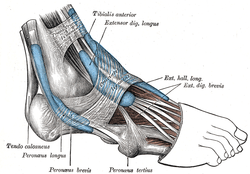

The mucous sheaths of the tendons around the ankle. Lateral aspect. (Ext. hall. long. labeled at upper left.) | |

The fibers pass downward, and end in a tendon, which occupies the anterior border of the muscle, passes through a distinct compartment in the cruciate crural ligament, crosses from the lateral to the medial side of the anterior tibial vessels near the bend of the ankle, and is inserted into the base of the distal phalanx of the great toe.

Opposite the metatarsophalangeal articulation, the tendon gives off a thin prolongation on either side, to cover the surface of the joint.